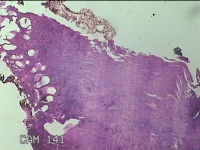

左大拇指红色赘生物

性别

男

年龄

75岁

临床诊断

病毒性疣?

一般病史

灰白粉红色肿物0.5x0.3x0.2cm一个,表面糜烂。

标本名称

大体所见

左大拇指起红色赘生物1年。

图2

皮角